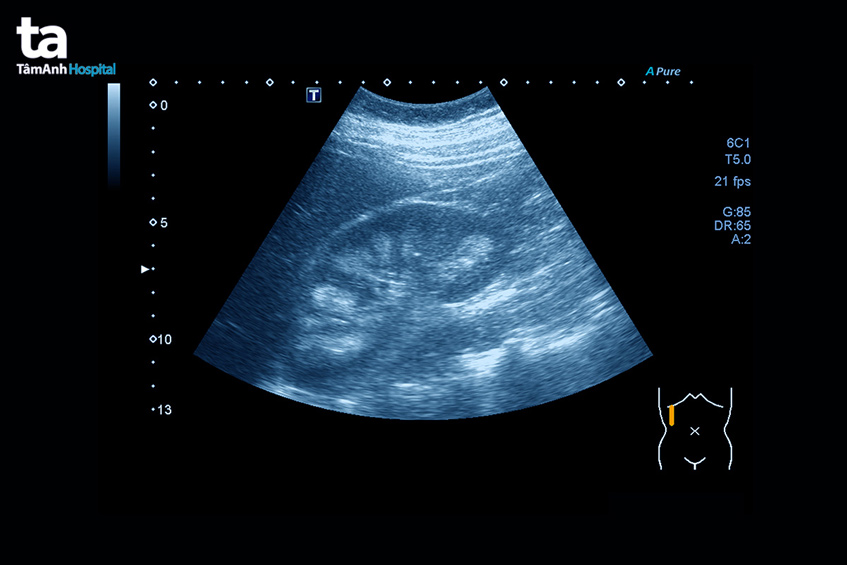

- Siêu âm: Phương pháp chẩn đoán này giúp phát hiện tình trạng thận ứ nước do tắc nghẽn niệu quản. Khi thận bị ứ nước hai bên có khả năng gây suy thận cấp tính hay mạn tính, phát hiện những trường hợp bệnh thận đa nang bẩm sinh, di truyền. Nếu hình ảnh siêu âm cho thấy thận có kích thước nhỏ, thay đổi cấu trúc, có nhiều nang hay mất phân biệt vỏ tủy…, đây là các dấu hiệu của bệnh thận mạn tính. Ngoài ra, siêu âm cũng giúp bác sĩ phát hiện tình trạng sỏi thận hay khối u trong thận.